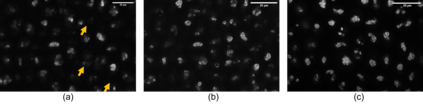

With the fast development of modern microscopes and bioimaging techniques, an unprecedentedly large amount of imaging data are being generated, stored, analyzed, and even shared through networks. The size of the data poses great challenges for current data infrastructure. One common way to reduce the data size is by image compression. This present study analyzes classic and deep learning based image compression methods, and their impact on deep learning based image processing models. Deep learning based label-free prediction models (i.e., predicting fluorescent images from bright field images) are used as an example application for comparison and analysis. Effective image compression methods could help reduce the data size significantly without losing necessary information, and therefore reduce the burden on data management infrastructure and permit fast transmission through the network for data sharing or cloud computing. To compress images in such a wanted way, multiple classical lossy image compression techniques are compared to several AI-based compression models provided by and trained with the CompressAI toolbox using python. These different compression techniques are compared in compression ratio, multiple image similarity measures and, most importantly, the prediction accuracy from label-free models on compressed images. We found that AI-based compression techniques largely outperform the classic ones and will minimally affect the downstream label-free task in 2D cases. In the end, we hope the present study could shed light on the potential of deep learning based image compression and the impact of image compression on downstream deep learning based image analysis models.